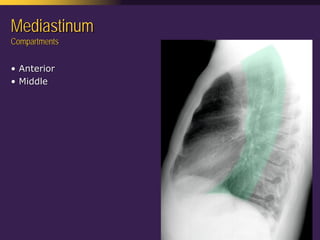

This document discusses mediastinal pathology using a compartmental approach. It describes the anatomy of the mediastinum and divides it into anterior, middle, and posterior compartments. Each compartment contains different structures and has a characteristic distribution of lesions. For example, 50% of lesions occur in the anterior compartment, which contains the thymus. The thymus is the most common site of lesions in the anterior compartment. Thymomas are the most common epithelial tumors of the thymus and mediastinum.